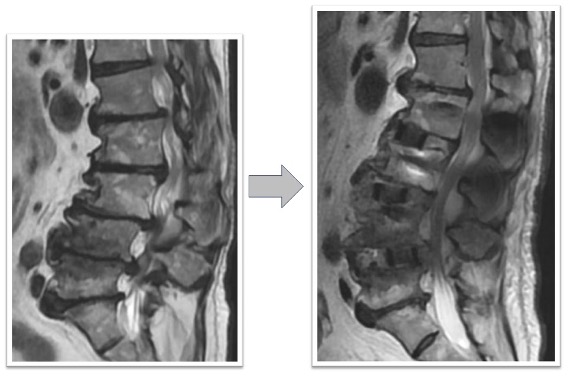

経皮的椎体形成術実例(*患者様の許可を得て掲載しています)

胸椎圧迫骨折

胸椎圧迫骨折後、遷延する腰痛と骨癒合不良を認めていた椎体に対してBKPを実施しています。治療後レントゲン画像では椎体内に注入された骨セメントと椎体高が改善していることが確認できます。腰痛改善し術翌日に退院となっています。